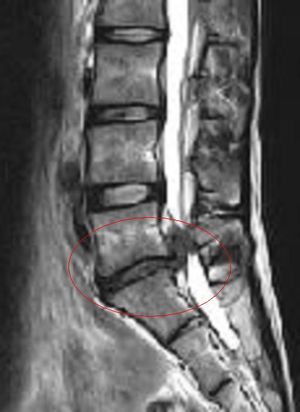

표시된 부분이 압박된 신경근]]3. 2. 감별 진단

'''빨간 원 안은 '압박된 신경근' 및 '수분 함량이 부족하고 염증을 일으켜 위로 크게 돌출된 추간판'''']]

'''위 이미지의 고농도 버전'''